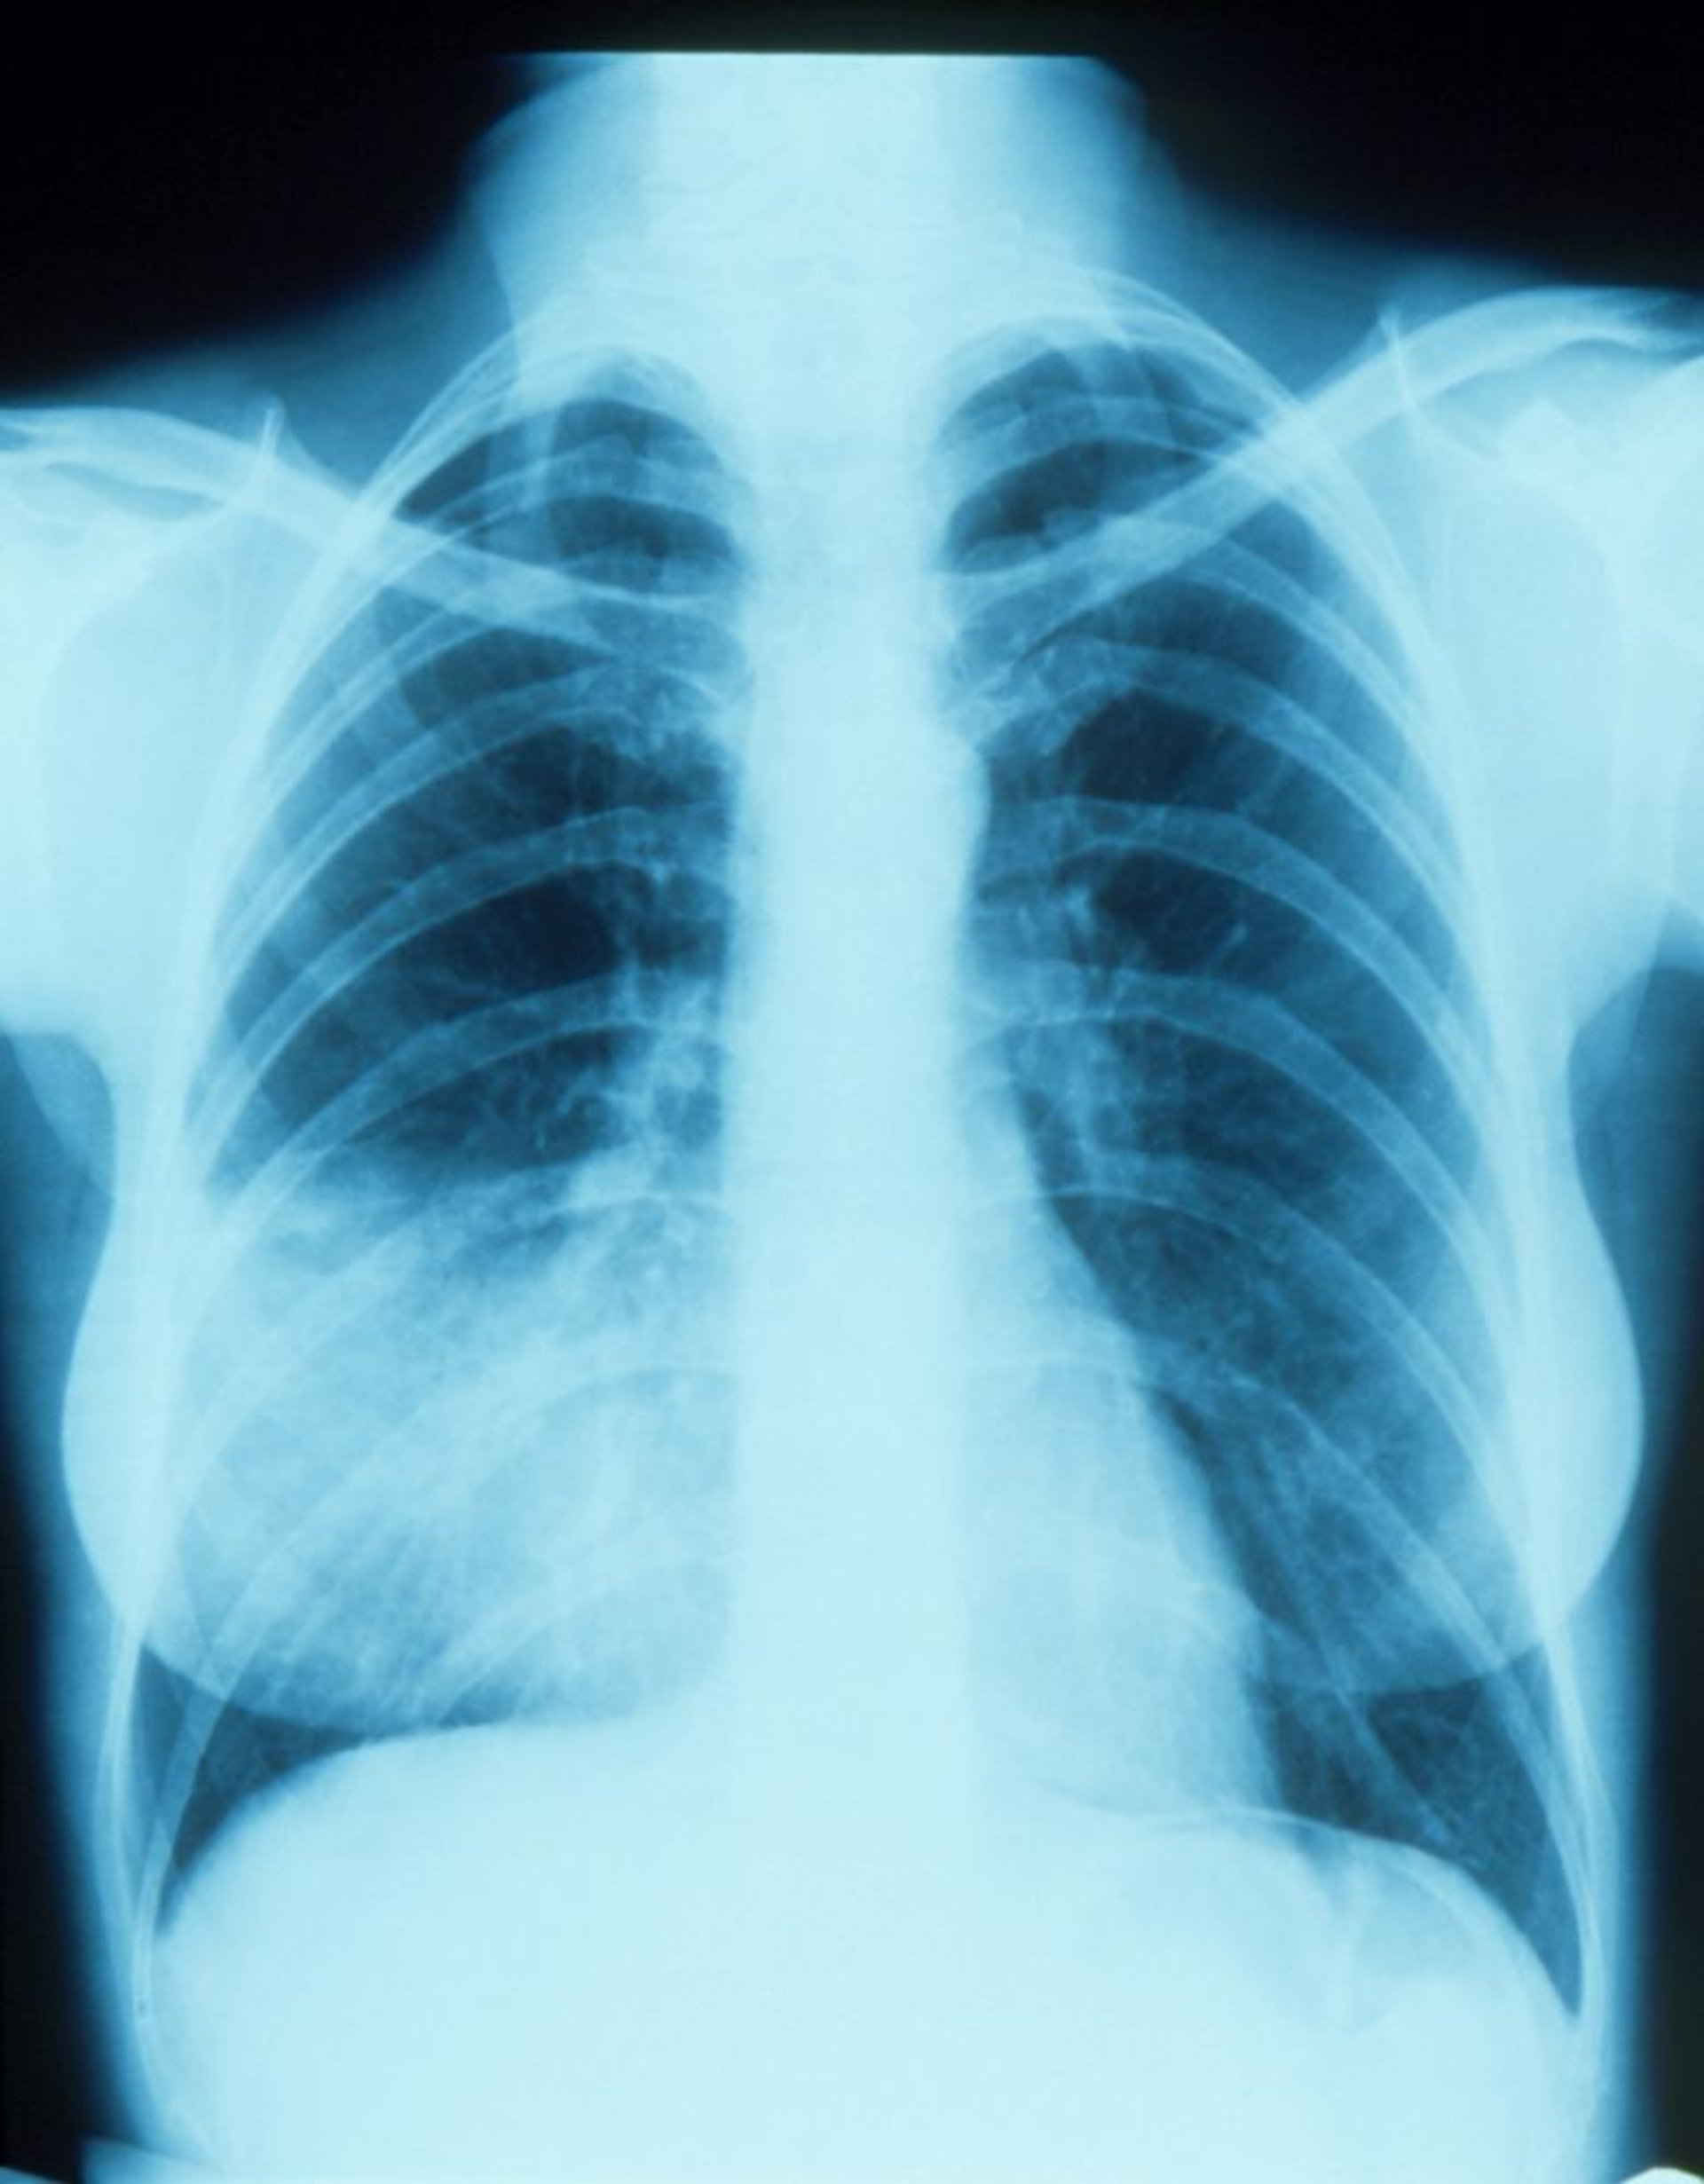

Neumonía del lóbulo medio derecho con signo de la silueta

Esta radiografía de tórax muestra un infiltrado que parece combinarse con el borde derecho del corazón (signo de la silueta). El signo de la silueta indica un posicionamiento contiguo de dos estructuras que tienen una radiodensidad similar; la parte del pulmón contigua al borde derecho del corazón es el lóbulo medio derecho, por lo que es la parte con el infiltrado y la neumonía.